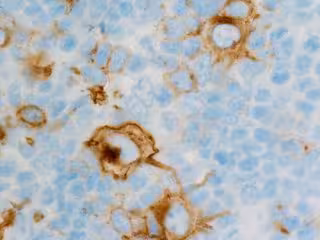

Linfoma de Hodking - FLIKR/CNICHOLSONPATH - Archivo